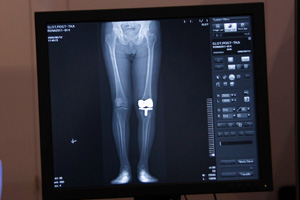

直接変換方式FPDを搭載した最上位機種「SONIALVISION safire 17」は,大視野FPD・超高精細画像の特長を生かしたアプリケーションが広がり,特に整形分野における“トモシンセシス”(オプション)が注目されている。米国でも,整形分野での金属アーチファクトの少なさが評価され,トモシンセシス撮影が行える同装置のニーズが高まってきているという。また,スロットラジオグラフィにより,歪みの少ない高画質な長尺画像を得ることができ,術前の治療計画における距離計測などに有用性を発揮する。

![]() 整形領域におけるトモシンセシス(人工関節の評価) |